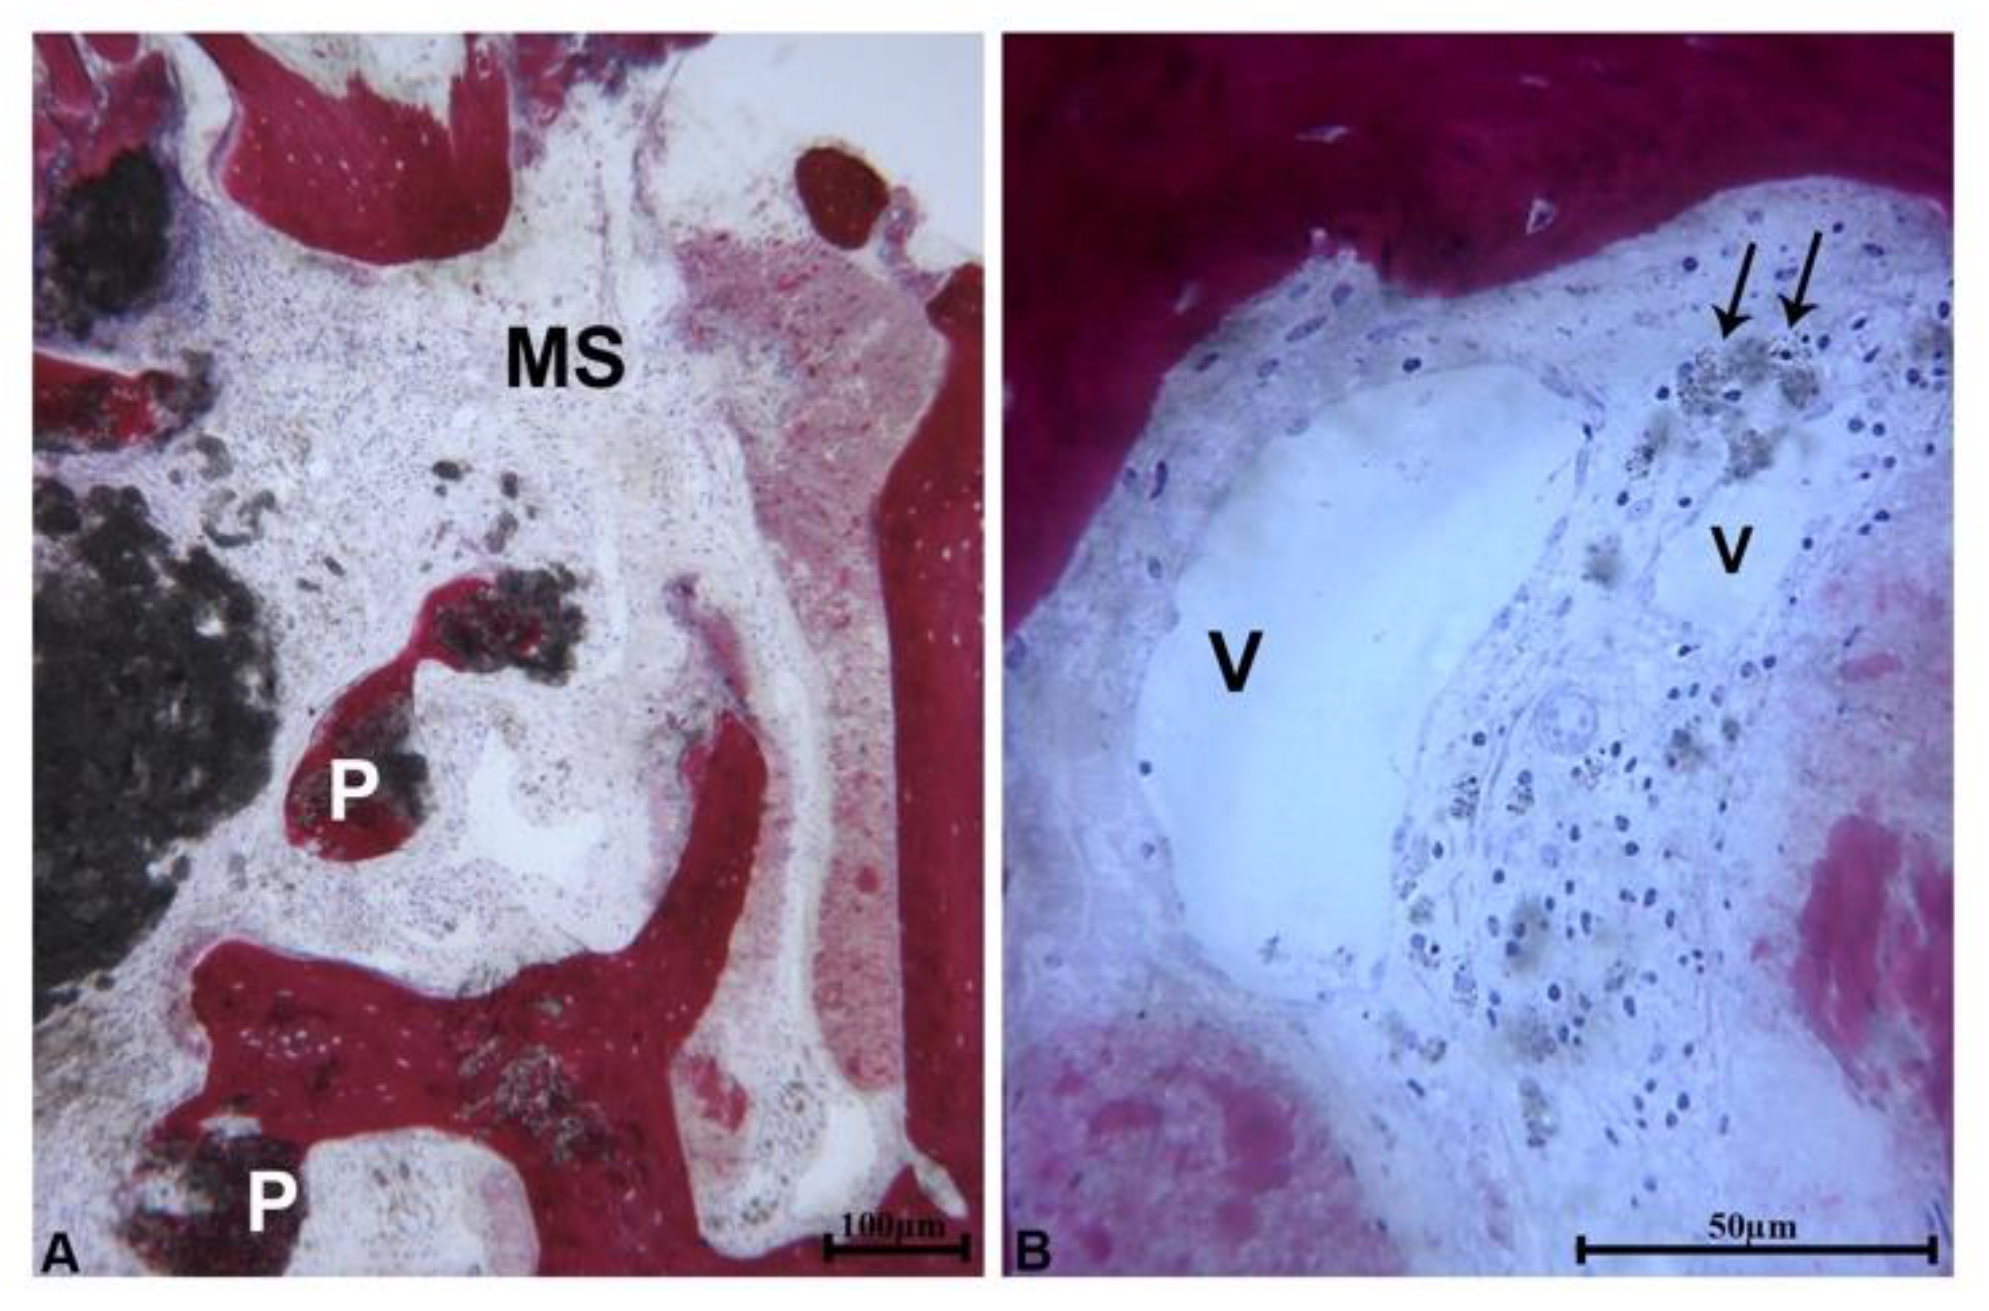

At low magnification, 3 samples showed a portion of bone wall consisting of pre-existing bone which lined the area of bone regeneration. Close to the pre-existing bone and in the apical portion of the samples, newly formed bone with small marrow spaces and residual biomaterial particles were present (

Figure 2a). In these portions of the samples, the residual biomaterial particles were embedded in the newly formed bone. These particles had an irregular shape and showed signs of resorption (

Figure 2b).